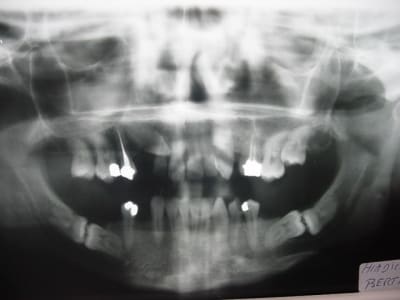

Le redressement d'emblee , au depart, en arc droit uniquement va abimer les dents piliers par effet retour, a mon avis.Sur le pano (tres net, bravo!) d'humator, on voit en plus qu'il existe une lyse osseuse de 2 a 4 mm horizontale qui ne joue pas en notre faveur de soignant.